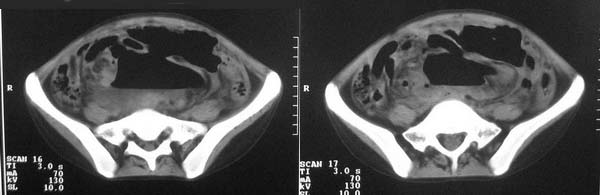

f-18y,腹痛,腹胀,停止排便排气4天,小便正常,四年前阑尾炎手术,病人已手术,明天上传结果。

乙状结肠也扩张

是不是直肠的问题

肠梗阻表现,有手术史,考虑粘连性可能

多考虑粘连性肠梗阻伴乙状结肠破裂可能。

直肠左侧低密度模糊影,乙状结肠明显扩张,有宽大液平,下腹部肠袢欠规整,内有多发小液平,结合有阑尾炎手术史考虑:直肠周围脓肿,低位肠梗阻,肠粘连。